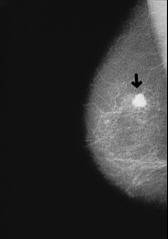

El organismo del grupo A está propenso a la mayoría de clases de cáncer, quiere decir a todas las clases de cáncer que tienen células similares a células corporales del grupo A.

Ejemplo: Radiografía con cáncer de mama

Caracoles contra cáncer de mama del grupo sanguíneo A

El caracol (Helix pomatia) contiene una lectina con un gran efecto contra las células de cáncer de mama que se comportan de manera similar a las células del cuerpo del grupo sanguíneo A (4 estrategias p.111).

Dr. D'Adamo indica:

<El caracol (Helix pomatia) contiene, como vamos a ver en el capitulo 10 [ver cáncer según grupo sanguíneo] una lectina con un efecto fuerte que coagula células mutadas cancerogenas, y las atrae al tipo A. Se trata de una clase positiva de coagulación porque esa lectina elimina las células enfermas.> (4 estrategias p.111)